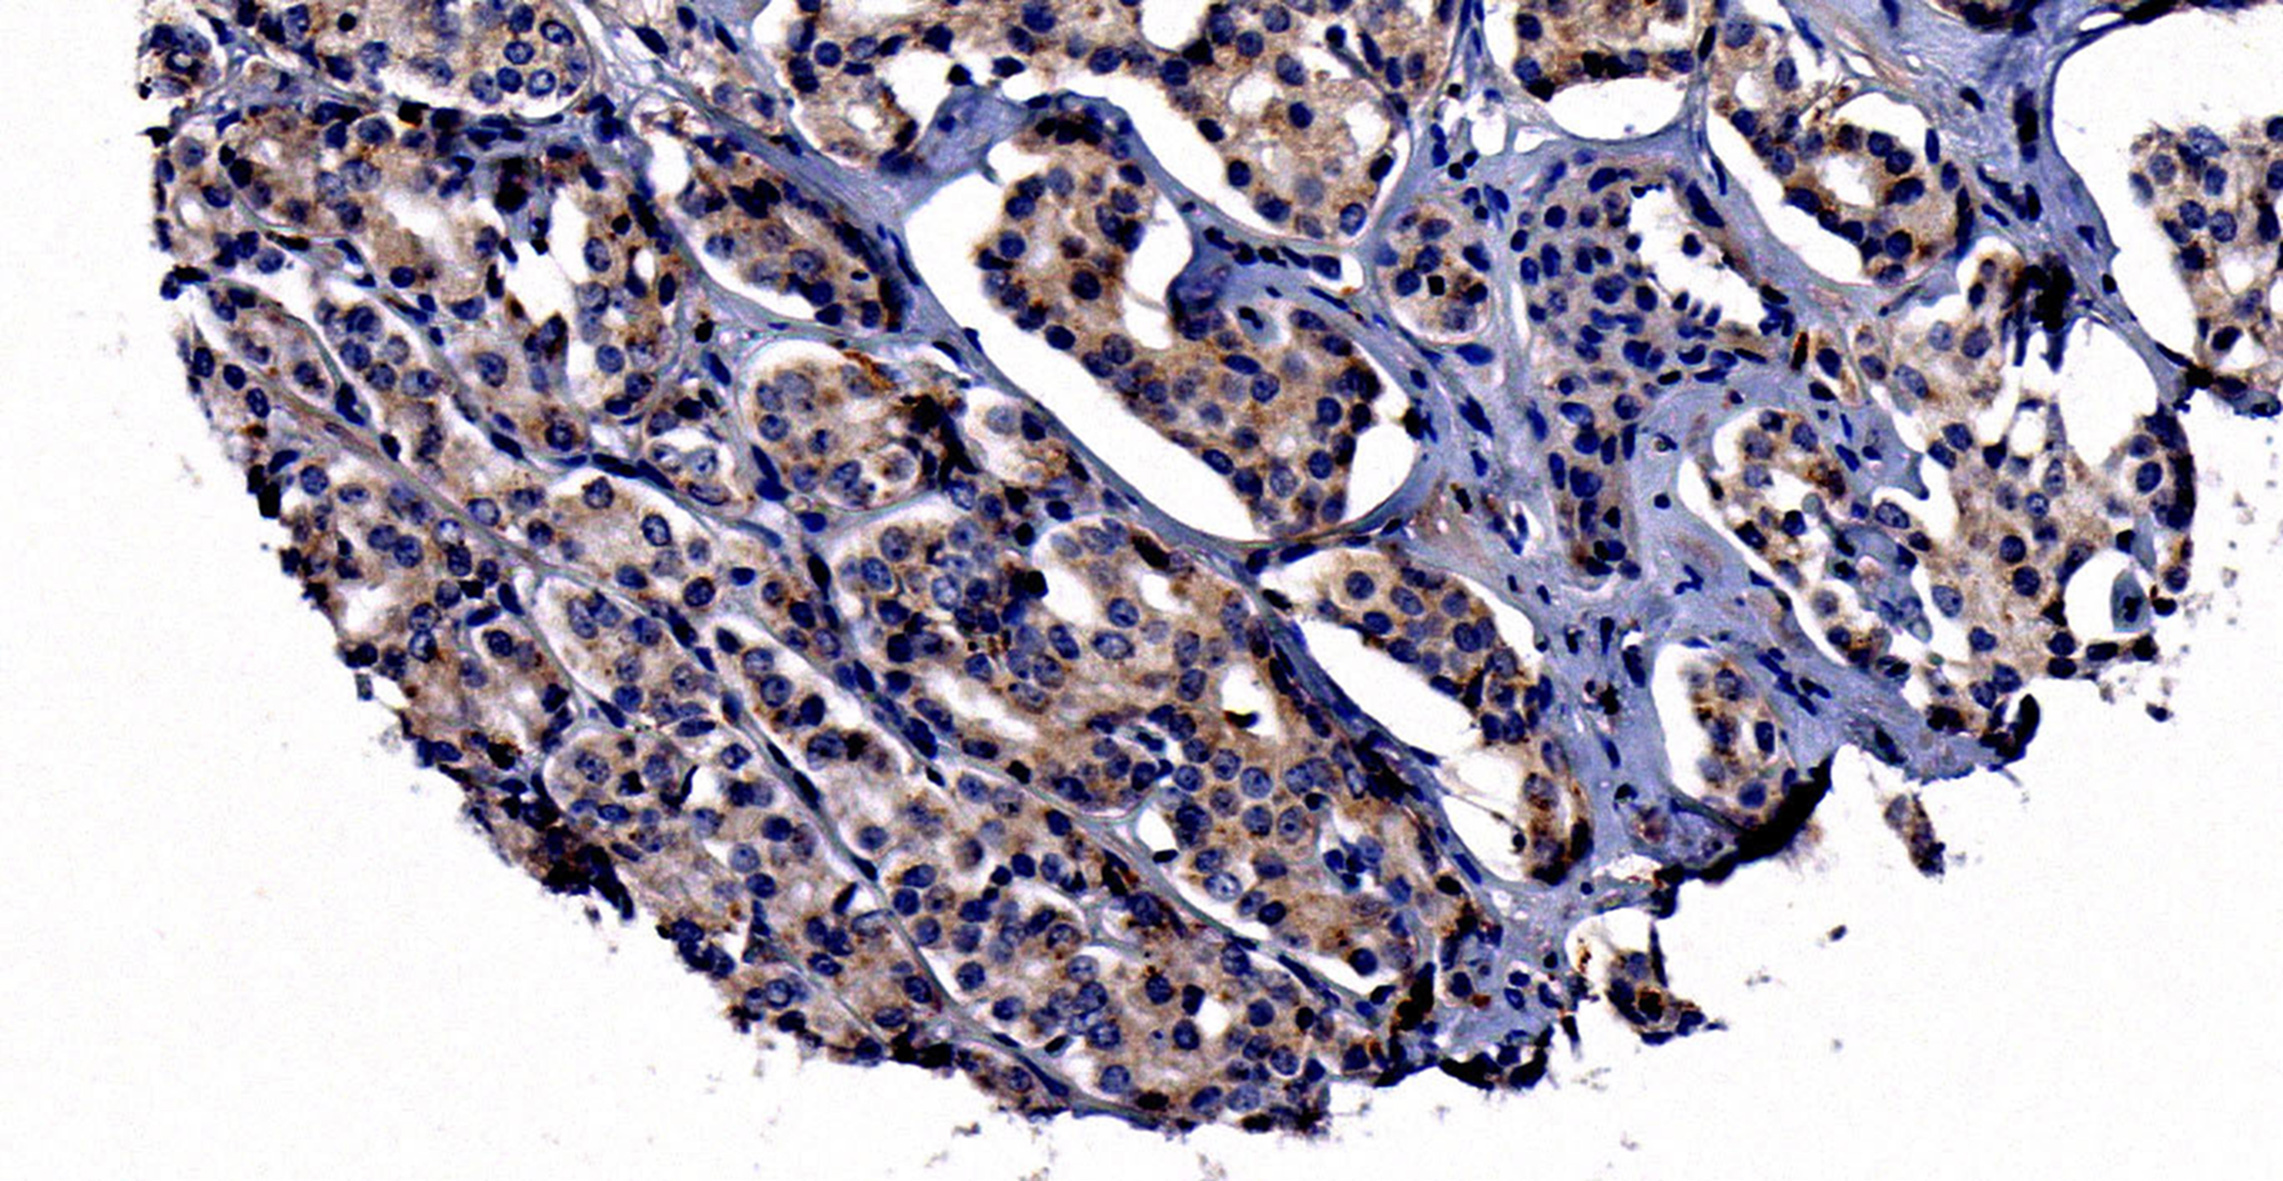

Zusammen mit seinen Kollegen aus der Pathologie der Mayo Clinic begutachtete Prof. Muders Gewebe, das sowohl aus dem Krebs in der Prostata als auch aus den Knochenmetastasen stammte. “Dabei zeigte sich, dass insbesondere die Metastasen viel Neuropilin 2 enthielten”, schildert Prof. Muders seine Forschungsergebnisse. „Daneben konnten wir zeigen, dass auch spezialisierte Knochenzellen, die sogenannten Osteoklasten, viel Neuropilin 2 aufweisen“, sagt Prof. Datta, zusammen mit Muders Korrespondenzautor der Studie. Daraus schlossen die Wissenschaftler, dass NRP2 bei der Absiedlung der Prostatakarzinome in das Skelett eine wichtige Rolle spielt.